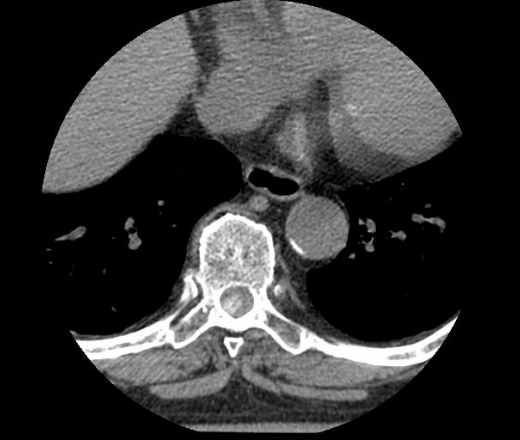

В течение 3-х месяцев отсутствие чувствительности и движений в нижних конечностях, тазовые нарушения. Осмотрена неврологом, назначено КТ.

На уровне Th7-Th8 в спинном мозге определяется образование в диаметре 13мм с четкими контурами, плотностью 250HU

КТ грудного отдела позвоночника ID:64474

Склоняюськ тому что это метастаз. Прошу вашего мнения коллеги.

На менингиому не похоже?

Менигеома вроде как должна расти экстрамедуллярно и сдавливать спинной мозг.

На что-то сосудистое не похоже?

Рассмотрите вариант обызвествленной туберкуломы спинного мозга. Очень похоже.